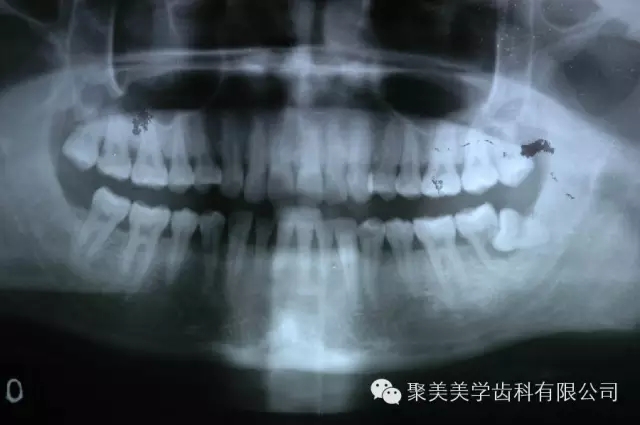

阻生牙把前面的牙齒頂壞了,兩個(gè)牙齒都需要拔除!

640.webp (1).jpg

放大看!

640.webp (2).jpg

被阻生牙頂壞的相鄰牙無(wú)法治療,只能拔除了,非常可惜!